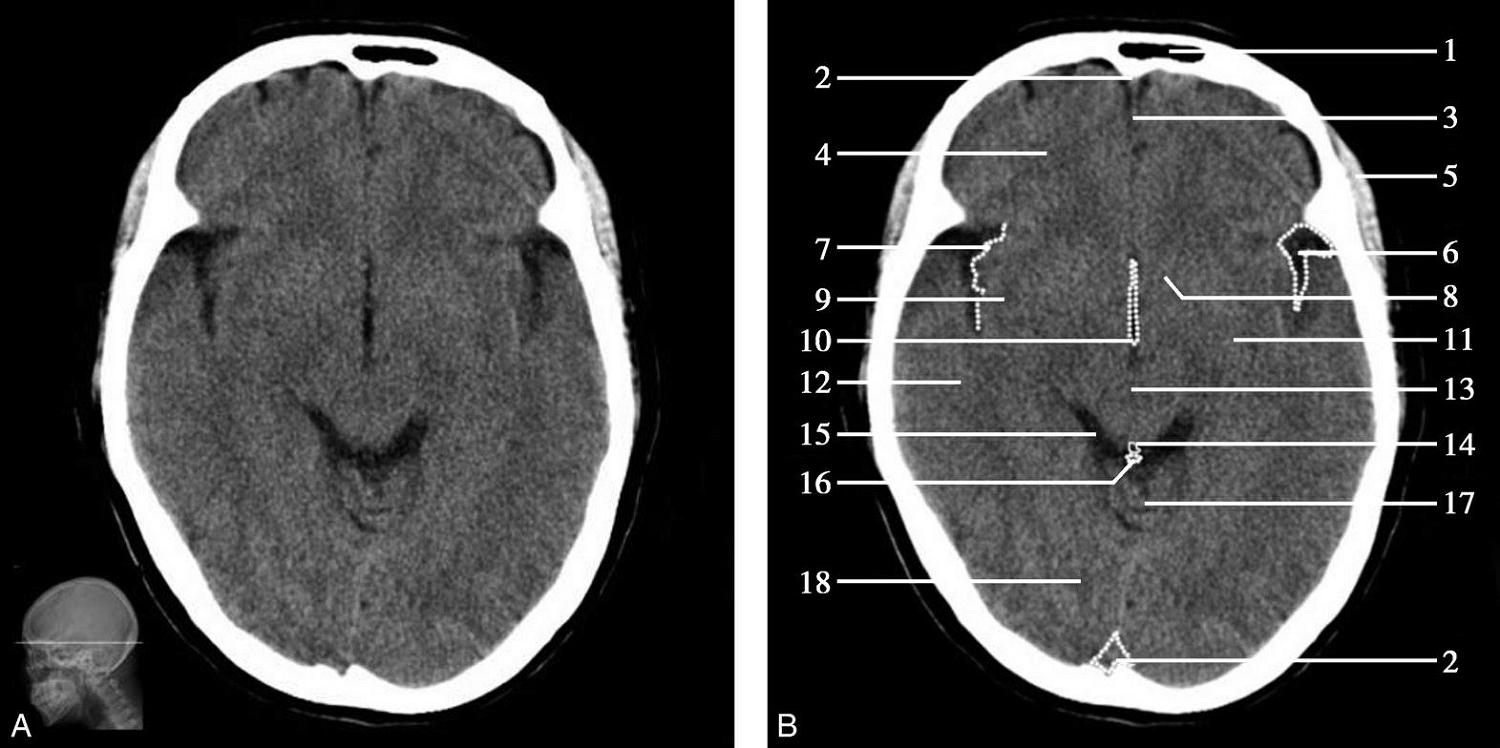

图1-2-29 基底节层面

A.横断面;B.横断面标注

1.上矢状窦;2.大脑镰;3.额叶;4.扣带回;5.颞肌;6.胼胝体膝部;7.侧脑室前角;8.岛叶;9.尾状核头部;10.外囊;11.透明隔;12.中央沟;13.中央前回;14.中央后回;15.内囊前肢;16.内囊膝部;17.穹窿柱;18.豆状核;19.内囊后肢;20.丘脑;21.大脑内静脉;22.胼胝体压部;23.大脑大静脉;24.颞叶;25.脉络膜丛;26.顶叶;27.侧脑室三角区;28.顶枕沟;29.视辐射;30.枕叶;31.直窦

基底节为脑卒中的好发部位,与纹状动脉的解剖特点有关,深穿支动脉的破裂和栓塞可分别引起基底节区的出血和梗死(图1-2-32、图1-2-33)。

图1-2-32 脑出血

A.右侧壳核脑出血,形成高密度血肿(★);B.右侧丘脑出血,呈球形高密度影(箭)

图1-2-33 基底节区脑梗死

A.右侧丘脑梗死,病灶呈圆形低密度影(箭);B.左侧内囊膝部及后肢梗死,呈带状低密度影(箭)